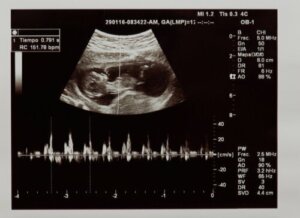

Med hjärtfrekvens syftar vi på antalet gånger hjärtat drar ihop sig under en minut. Fostrets hjärtfrekvens kan identifieras under de första veckorna av graviditeten med hjälp av ett ultraljud, eller en mätare som kallas doppler.

Först kommer ultraljudsteknikern att bedöma om hjärtslag verkligen är närvarande och på så sätt kontrollera fostrets vitalitet. Dessutom utvärderar de hur många gånger hjärtat slår under en minut. De värden som anses normala i fosterstadiet är mellan 120 och 160 slag per minut.